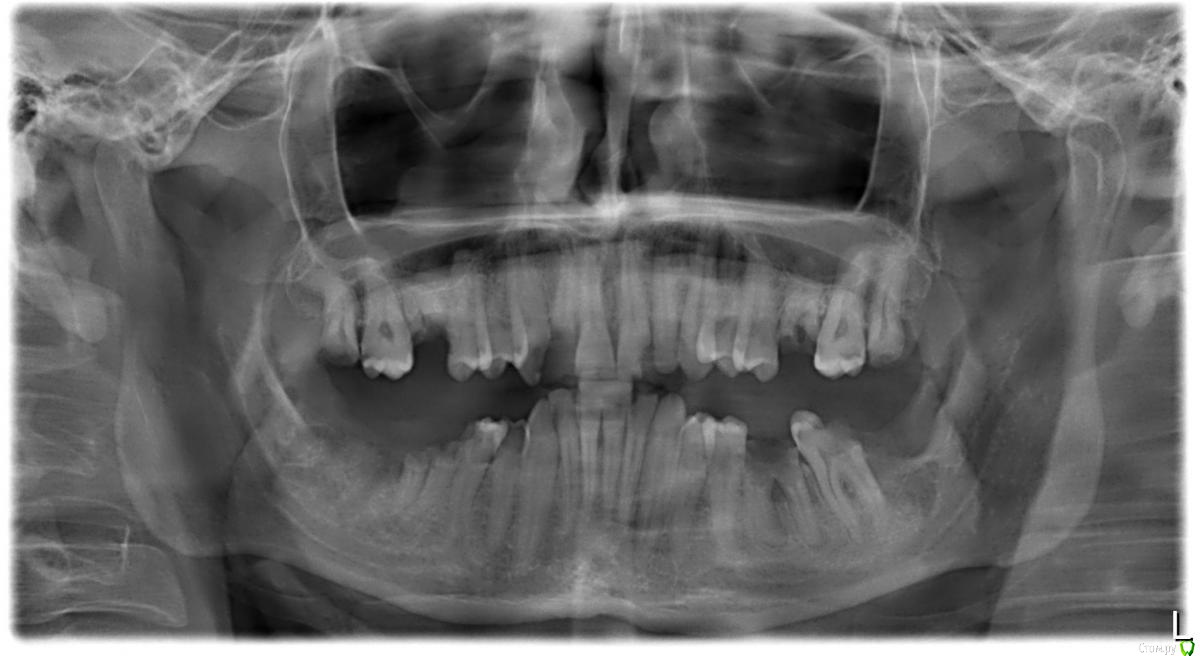

Евгений 717 Опубликовано 15 октября, 2018 Поделиться Опубликовано 15 октября, 2018 (изменено) Здравствуйте. Предстоит удаление 6-х и 8-х верхних зубов. Существует ли риск перфорации пазухи? Или точнее высокий ли риск перфорации? Изменено 15 октября, 2018 пользователем Евгений 717 Ссылка на комментарий

Bier Опубликовано 15 октября, 2018 Поделиться Опубликовано 15 октября, 2018 Риск не высокий. Главное аккуратно удалять. 1 Ссылка на комментарий